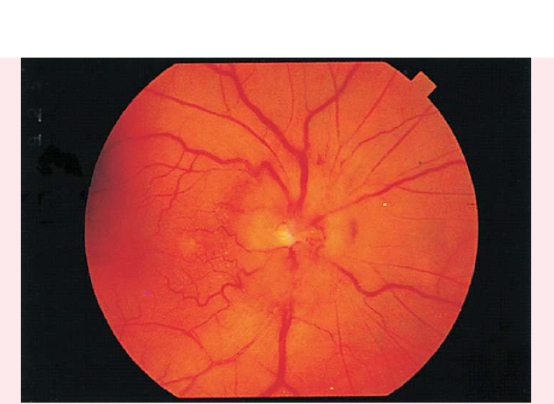

PAPILLEDEMA

Swollen optic disc

Blurred margins

Hyperemic appearance from accumulation of excess blood

Visible and numerous disc vessels

Lack of visible physiologic cup